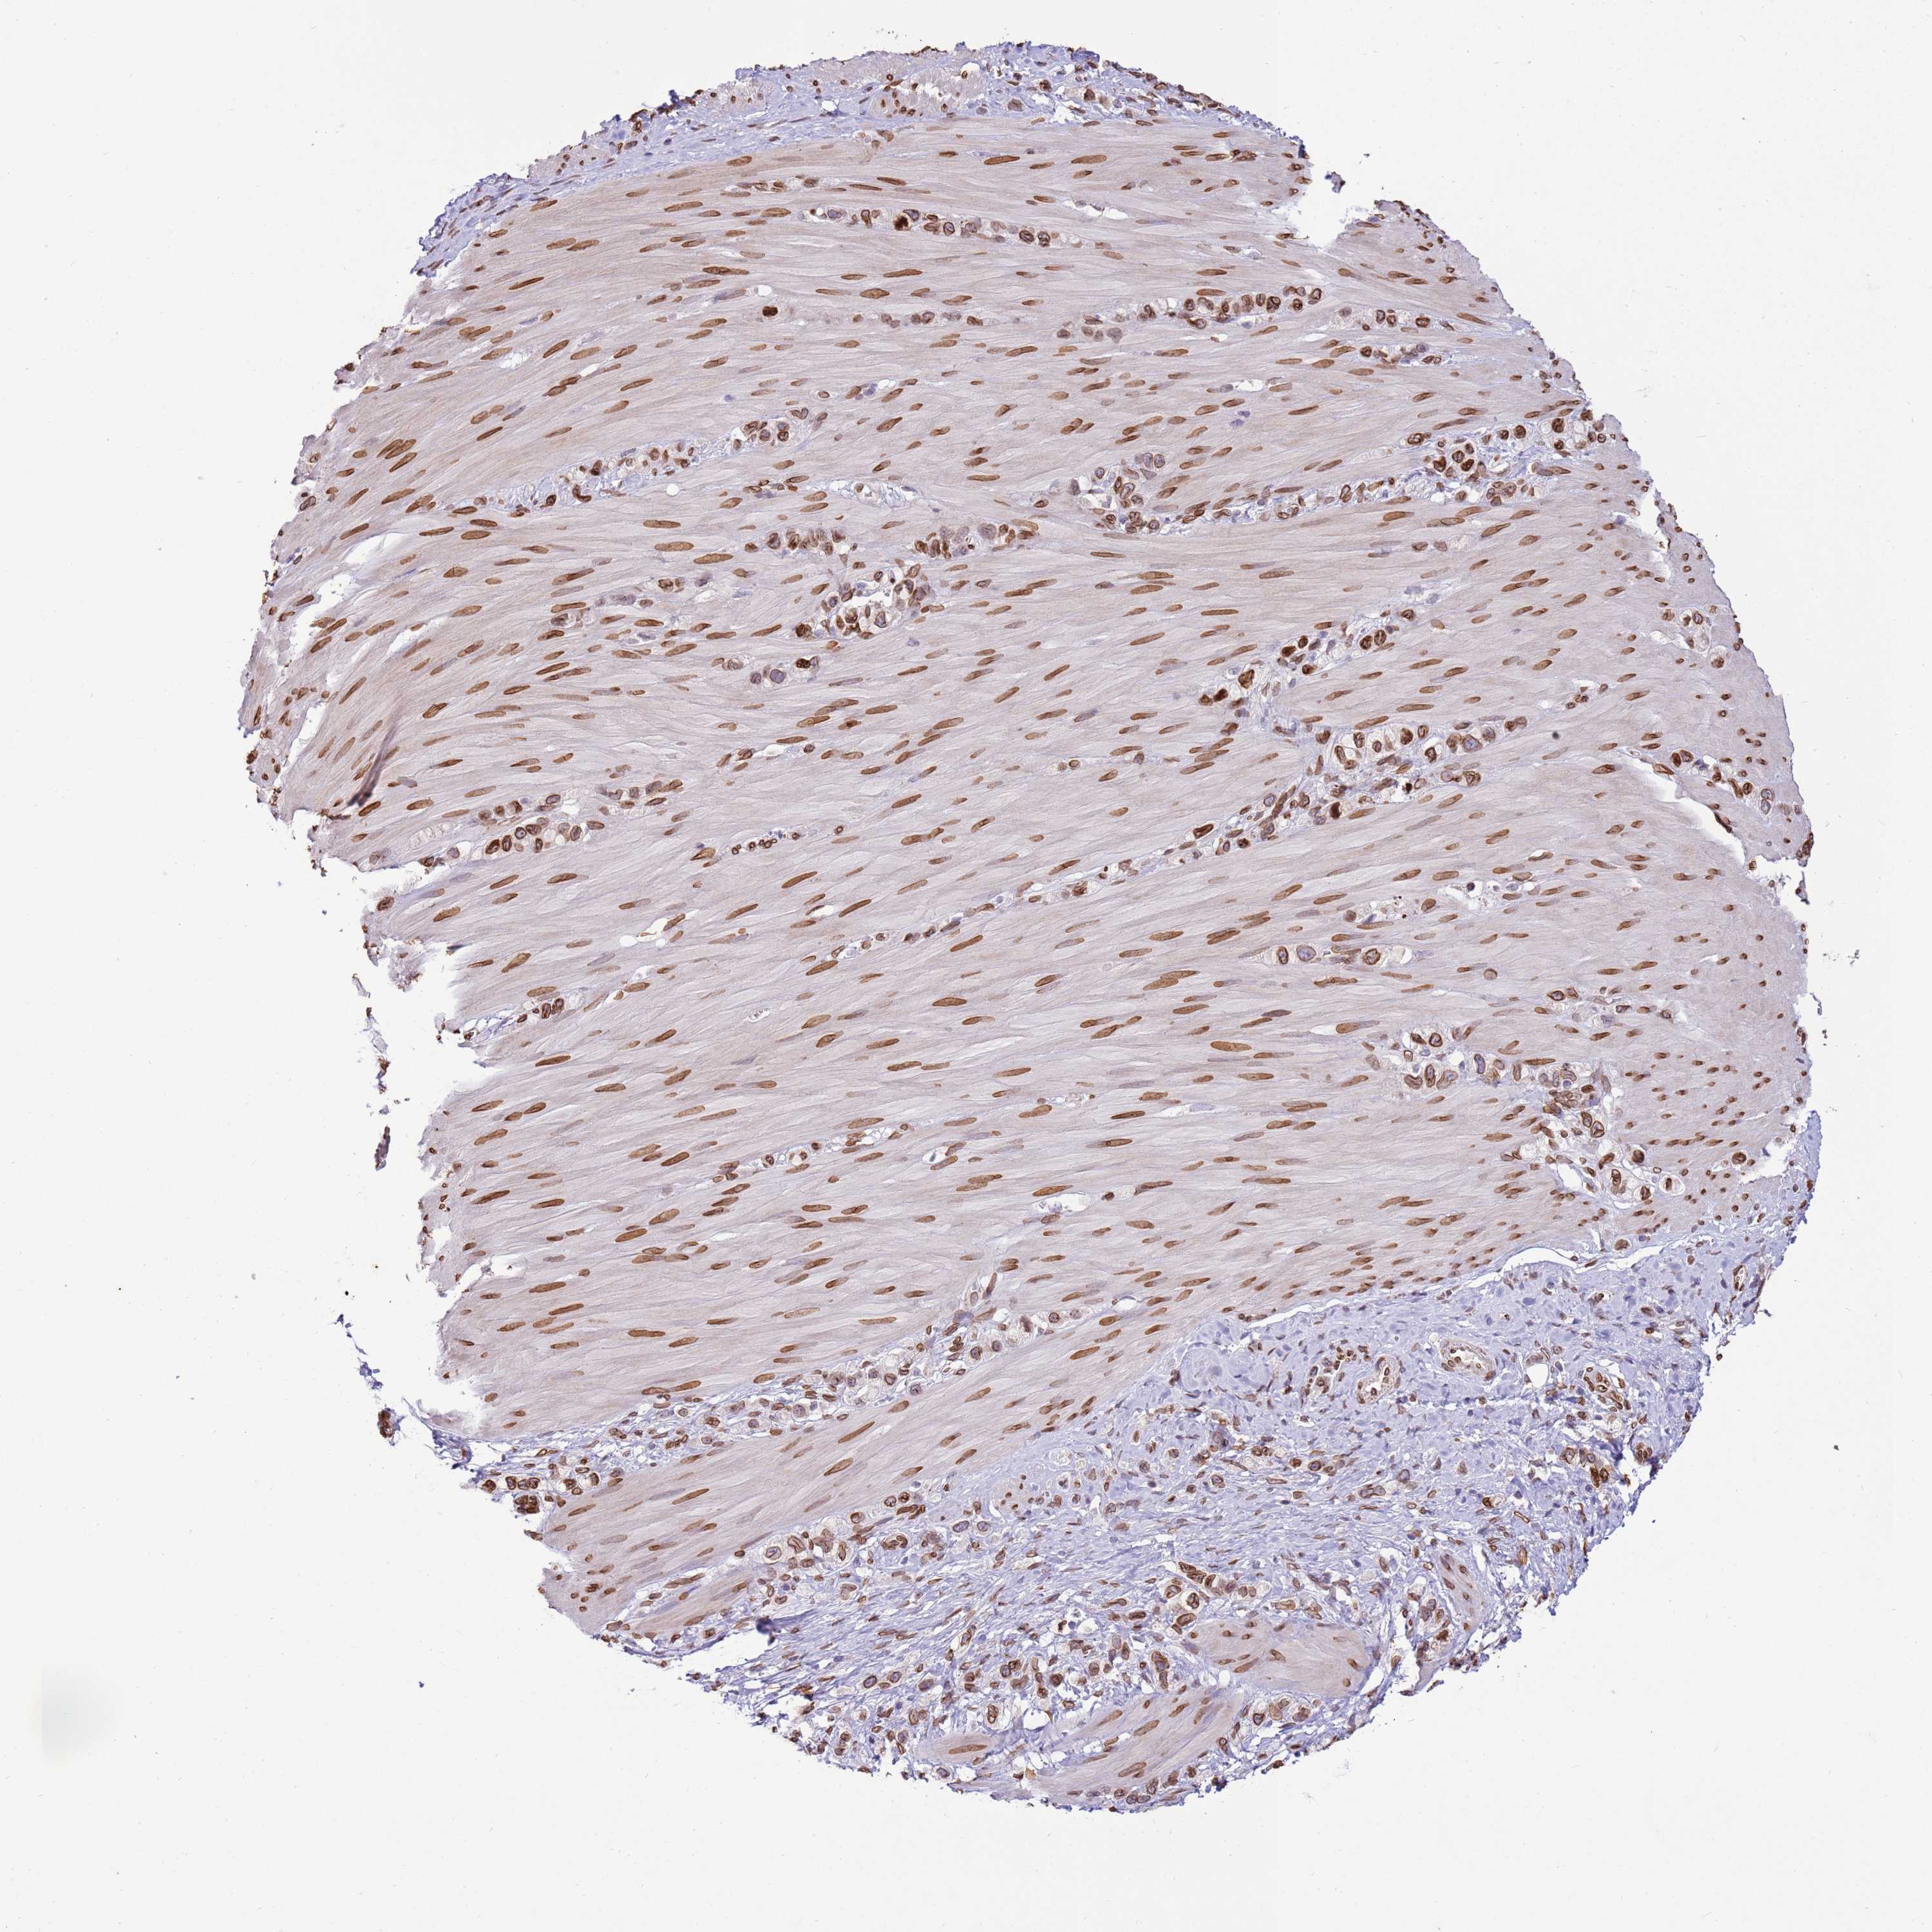

STOMACH CANCER - Protein expressioni

A mouse-over function shows sample information and annotation data. Click on an image to view it in a full screen mode. Samples can be filtered based on level of antibody staining by selecting one or several of the following categories: high, medium, low and not detected. The assay and annotation is described here.

Note that samples used for immunohistochemistry by the Human Protein Atlas do not correspond to samples in the TCGA dataset.

Antibody stainingi

Antibody staining in the annotated cell types in the current human tissue is reported as not detected, low, medium, or high, based on conventional immunohistochemistry profiling in selected tissues. This score is based on the combination of the staining intensity and fraction of stained cells.

Each image is clickable and will lead to virtual microscopy that enables deeper exploration of all samples and also displays staining intensity scores, fraction scores and subcellular localization as well as patient and tissue information for each sample.

Antibody HPA046658

Staining

High

Medium

Low

Not detected

Intensity

Strong

Moderate

Weak

Negative

Quantity

>75%

75%-25%

<25%

None

Location

Nuclear

Cytoplasmic/membranous

Cytoplasmic/membranous,nuclear

Adenocarcinoma, NOS